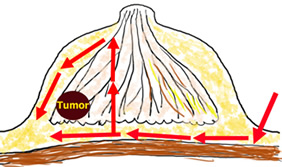

従来の乳腺内視鏡手術は、皮膚直下を剥離することにより手術操作を行っていましたが、剥離範囲が広くなると知覚神経の損傷もひどくなります。この方法は、全て腋窩の傷のみから操作し、乳腺の背側から腫瘍部分の乳腺を切除してきますので、神経損傷や皮膚障害が起こりません。また、乳房のどの位置に腫瘍があっても手術可能です。乳輪縁切開では乳頭・乳輪の変形を起こす可能性がありましたが、その心配もいりません。

腋窩に2.5 cmの皮膚切開(腫瘍の位置によって乳輪縁にも2.5cm)を施し、5 mmのビデオスコープを使い、モニターで見ながら、手術操作を行います。癌病巣を周囲1~2 cmの乳腺組織とともに切除します。さらに、腋窩リンパ節郭清を行います。乳腺の欠損部分は周囲の脂肪組織を寄せたり、側胸部脂肪織や人工合成繊維網を充填して、形を整えます。腋窩リンパ節郭清を行う場合には腋窩のリンパ液漏出に対して、J-VACドレーンを留置します。皮膚は、吸収糸で皮下縫合し、表面はダーマボンドという接着剤で固定します。これにより、傷を完全に密閉出来ますので、水に濡らしても平気ですし、傷の消毒・抜糸は要りません。傷は、腋の下に隠れる目立たないところに、わずか2~3cmの小ささで、しかも綺麗に出来上がりますので、皆さんが満足されています。

乳管内非浸潤癌(DCIS)で、乳管内進展が強く、乳腺の広範囲に広がっている場合には、どうしても温存手術をすることができません。かといって、非常に早期のがんですから、乳房切断術を行うのは、過剰の手術ということになります。我々は内視鏡を用いることにより、乳頭と皮膚を切除することなく、乳腺全摘+乳房再建術を行っています。人工物を使いますので、新たに傷を付けることはありません。でき上がりは、左右対称で違和感はありません。今後積極的に行っていく予定です。